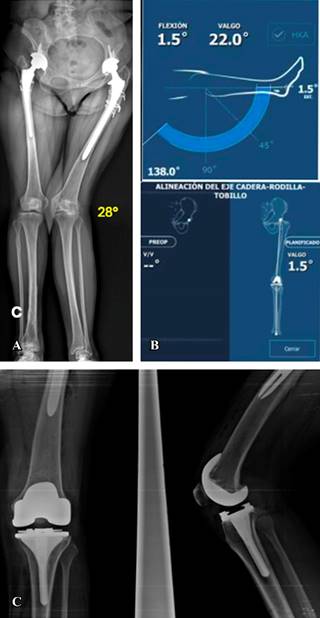

Dieciséis casos presentaron deformidad en valgo (Figuras 2 y 3) con un promedio de 11.88o de deformidad. En cuatro casos la alineación final fue en varo con un promedio 1.87o; en nueve la alineación final fue con un valgo promedio de 1.66o y en tres casos la alineación fue neutra. El cambio en los grados promedio de la serie entre la deformidad inicial y la alineación final fue estadísticamente significativo (p = 0.005) en el análisis de covarianza.

Figura 3: A) Eje mecánico de los miembros inferiores de un caso con un vástago para artroplastía de revisión no cementada de cadera izquierda y deformidad angular de rodilla en valgo de 28o en la rodilla ipsilateral. B) Análisis de movilidad y alineación postoperatoria con cirugía robótica (rango de movilidad de 1.5 a 138o) y alineación final en valgo de 1.5o. C) Radiografía postoperatoria con prótesis de rodilla estabilizada posterior y vástago tibial de 80 mm.